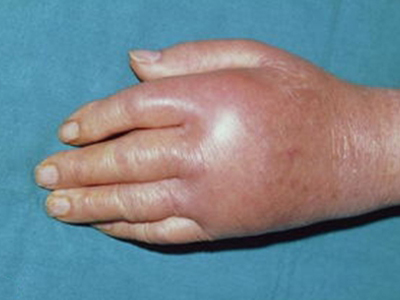

痛风急性发作时,表现为关节红肿、灼痛、感觉过敏、活动受限,伴畏寒、发热、头痛、乏力和纳差等症状。常于夜间发作,白天缓解,入夜又发,经几日到几周发作而逐渐停止,关节疼痛缓解。